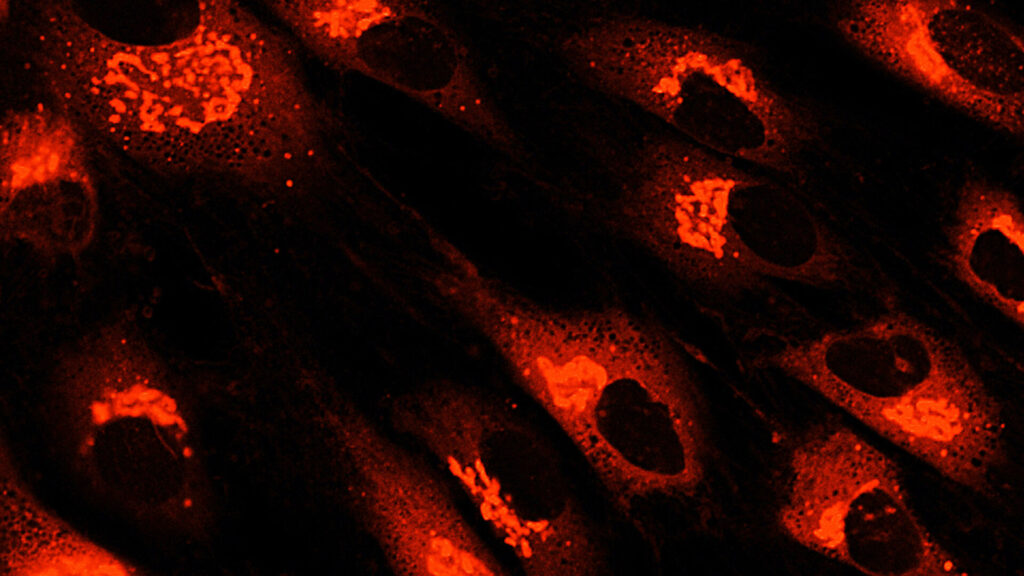

如今,MSC一詞描述了一類細胞,歷史上被稱為間充質(zhì)干細胞、間充質(zhì)基質(zhì)細胞和醫(yī)學信號細胞等。間充質(zhì)干細胞的臨床用途主要歸因于它們的關(guān)鍵生物學特性,其中包括:

根據(jù)臨床前和臨床證據(jù),間充質(zhì)干細胞治療免疫和炎癥性疾病顯示出特別的前景,研究人員正在探索間充質(zhì)干細胞衍生療法和外泌體在治療自身免疫性疾病、骨關(guān)節(jié)炎、炎癥性肝病、肺部疾病、移植排斥等方面的臨床應用。人們對同種異體間充質(zhì)干細胞的興趣也日益濃厚,因為它可以作為現(xiàn)成產(chǎn)品提供。

如今,間充質(zhì)干細胞正在新興應用中得到應用,例如組織工程、類器官、外泌體生產(chǎn)、藥妝品和培養(yǎng)肉。此外,人們正在探索iPSC衍生的MSC在MSC療法開發(fā)中的作用,因為這些MSC可以經(jīng)濟地以幾乎無限的規(guī)模批量生產(chǎn)。